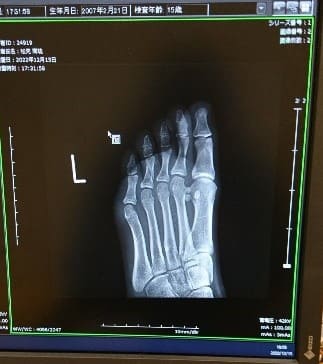

固定し、翌日整形外科に受診依頼を出し受診、レントゲンを確認すると…

このように骨折線が入っており、 診断結果は【第4趾基節骨脱臼骨折】でした。